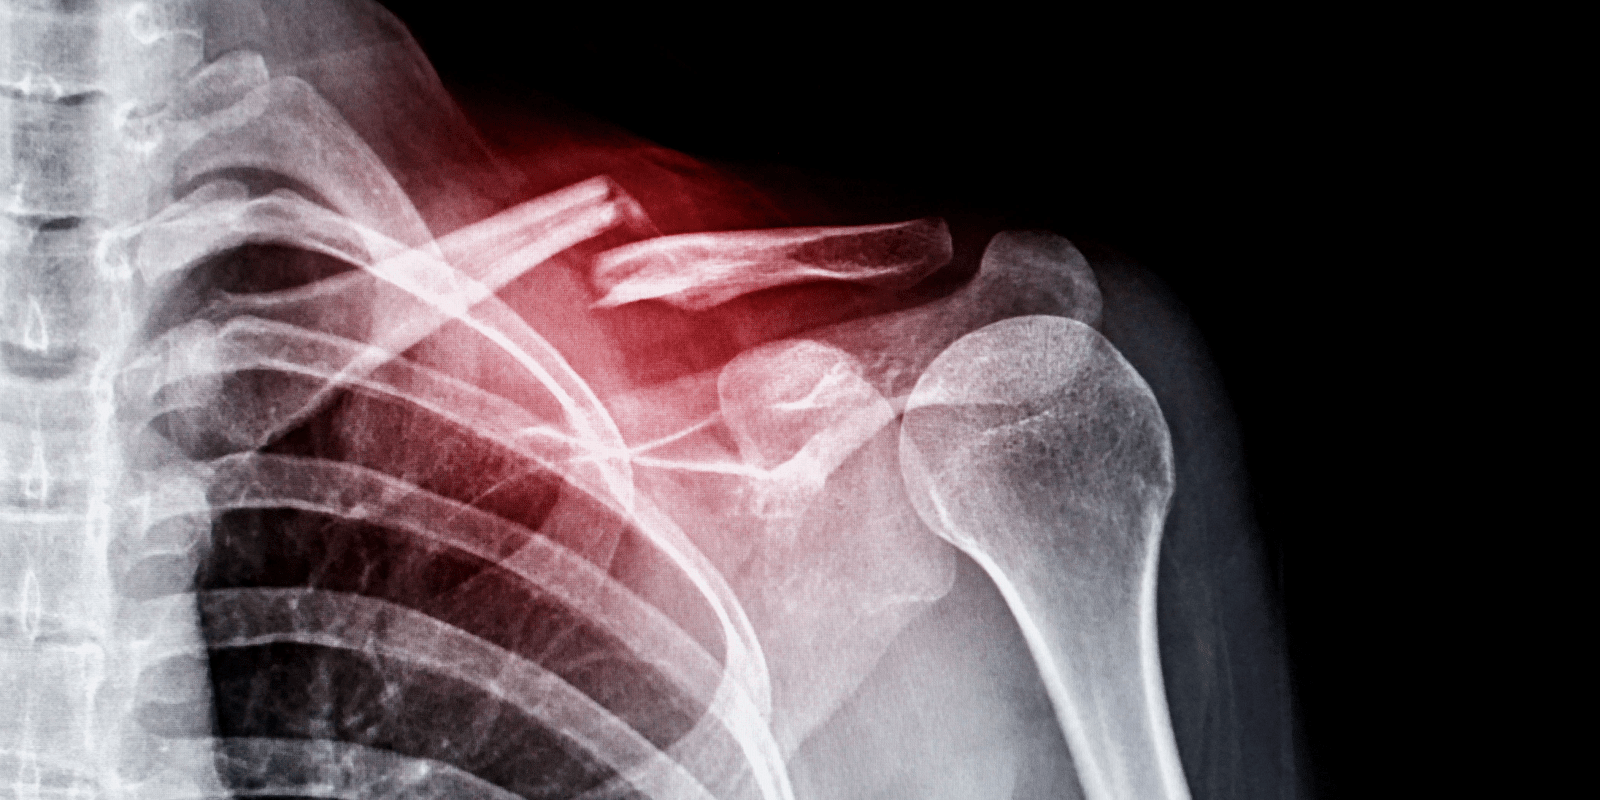

어깨 골절 수술과 물리치료

어깨뼈 골절이 심각할 경우, 수술을 통해 뼈를 고정시키고 빠른 회복을 도모할 수 있습니다. 수술 후에는 보통 깁스를 사용하지 않고, 고정된 뼈가 안정될 때까지 재활 치료를 시작합니다. 물리치료는 골절 부위의 기능을 회복하고 통증을 경감시키는 데 중요한 역할을 하며, 수술 후 즉시 시작할 수도 있습니다. 물리치료는 관절의 움직임을 개선하고 근육을 강화시키는 데 중점을 두며, 장기적으로는 전반적인 기능 회복을 목표로 합니다.